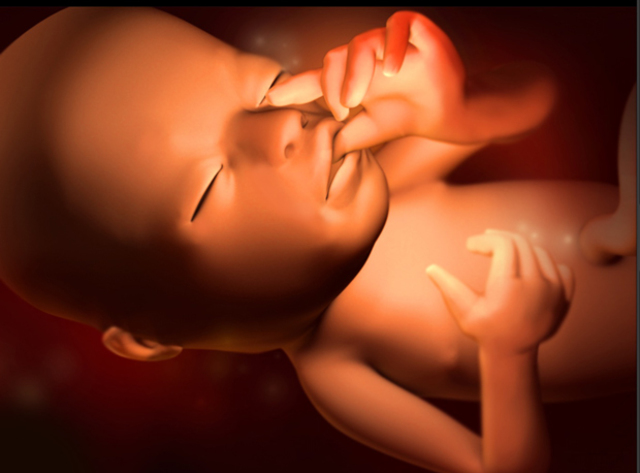

• Semana 15-18

Semana 15-18

Se forma lanugo en la cabeza del feto lo que simula cabello delgadito. Los huesos y el tejido muscular se van desarrollando en estas semanas para hacerse más fuertes. Para estas semanas, el bebé ya comienza a moverse y a estirarse. Inclusive, ya pueden hacer movimientos de succión y chuparse el dedo.